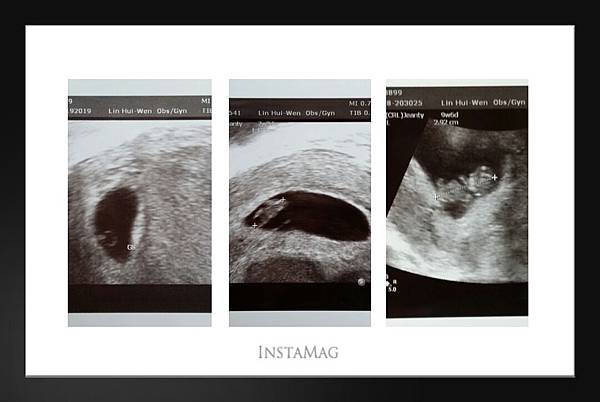

真的有比7w3d時大很多,看的出大頭、手、腳

圖(1) 5W 圖(2)7W3D 圖(3)9W5D